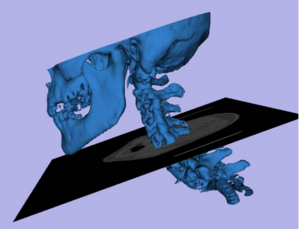

- 7.27 Integration of 3D Anatomical Data Obtained by CT Imaging and 3D Optical Scanning for Computer Aided Implant Surgery